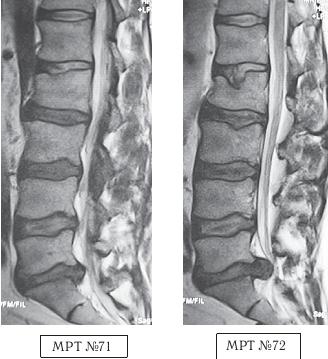

После второго сеанса боли у пациента усилились. Он обратился в районную больницу. Участковый травматолог направил больного на МРТ. Но вопреки здравому смыслу пациент отправился с результатами обследования (МРТ № 71) не к травматологу, а опять к тому же «костолому». Тот, внимательно посмотрев снимки, сказал, что ему «всё ясно», грыжа межпозвонкового диска «выпала вовнутрь, в живот» и что «обычно хватает одного-двух сеансов, но тут дело серьёзное и просто необходимо провести ещё один, а может и два сеанса». Пациент, по наивности своей, согласился. Всё повторилось как и в первые два раза, только этот «специалист» значительно усилил силу своего воздействия, когда посадил его на пол и начал толчками давить на плечи, очевидно, чтобы диск уж точно «вышел из живота и зашёл куда надо». Это называется: «сила есть, ума не надо». После нескольких таких толчков пациент почувствовал резкую боль («как разряд тока»), прошедшую от копчика до головы, ноги онемели. Через несколько дней у данного больного развились тазовые нарушения. Сделали повторное МРТ № 72. Результат более чем удручающий: компрессионный перелом тела позвонка LII, секвестрированная грыжа межпозвонкового диска в сегменте LV-SI, абсолютный стеноз спинномозгового канала.

На МРТ № 71 наблюдается сглаженность физиологического лордоза, грыжа межпозвонкового диска в сегменте LV—SI, спондилёз на том же уровне, множественные грыжи Шморля, стеноз.

На МРТ № 72 наблюдается помимо всего выше перечисленного ещё и компрессионный перелом тела позвонка LII и секвестрированная грыжа межпозвонкового диска в сегменте LV—SI, абсолютный стеноз спинномозгового канала.